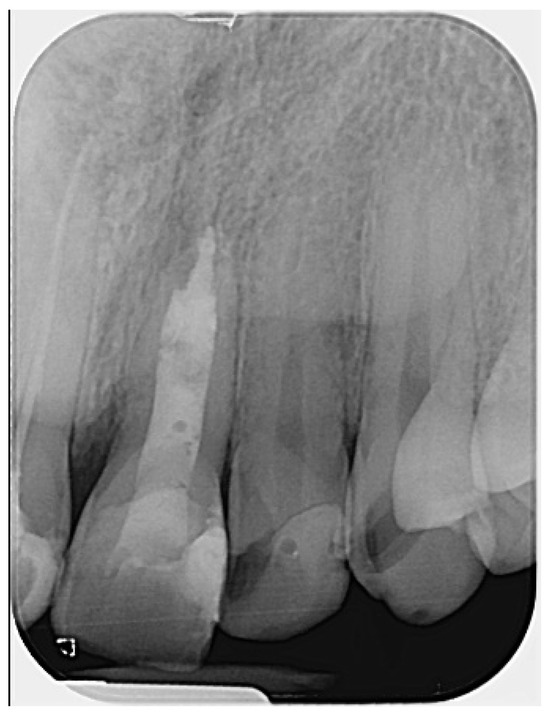

The working length was confirmed radiographically using an ISO size 80 gutta-percha cone (DiaDent, Cheongju, South Korea). Following this, the gutta-percha was removed, and calcium hydroxide dressing (Calcipast, Cerkamed, Stalowa Wola, Poland) was placed in the canal and left in situ for a period of two weeks (Figure 2).

Figure 2.

Radiographic verification of the working length confirmed accurate measurement during the clinical appointment. (The mark in the lower left corner indicates the left side.)

The radiographs also revealed some imperfections, such as slight inhomogeneity in the root canal filling and a small amount of radiopaque material extruded into the periapical area. This was first observed in the gutta-percha cone trial radiograph (Figure 2), where calcium hydroxide was visible beyond the apex. This is likely attributed to the presence of barium sulfate (BaSO4), a radiopacifier commonly incorporated into commercial calcium hydroxide pastes, which is known to resist resorption when displaced into periapical tissues [32]. Such extrusion can occasionally occur, particularly in cases involving large or chronic periapical lesions, or in teeth with open apices where the natural apical constriction is compromised. The radiopaque material remained visible in subsequent radiographs (Figure 2). It is also possible that the material observed in the later images corresponds to a small extrusion of the calcium silicate-based hydraulic cement used for the apical plug. The presence of this material did not result in any clinical symptoms or adverse effects, nor did it appear to interfere with the periapical healing process, as confirmed by radiographic follow-up. While this finding may be considered as a technical imperfection, it did not compromise the overall favorable outcome of the present case. Nevertheless, such issues should be avoided whenever possible. Although the treatment followed in this case was adapted to patient-specific constraints, and therefore may slightly deviate from standard endodontic protocols, it provides a clinical perspective on the potential for non-surgical healing in cases of apical fenestration.